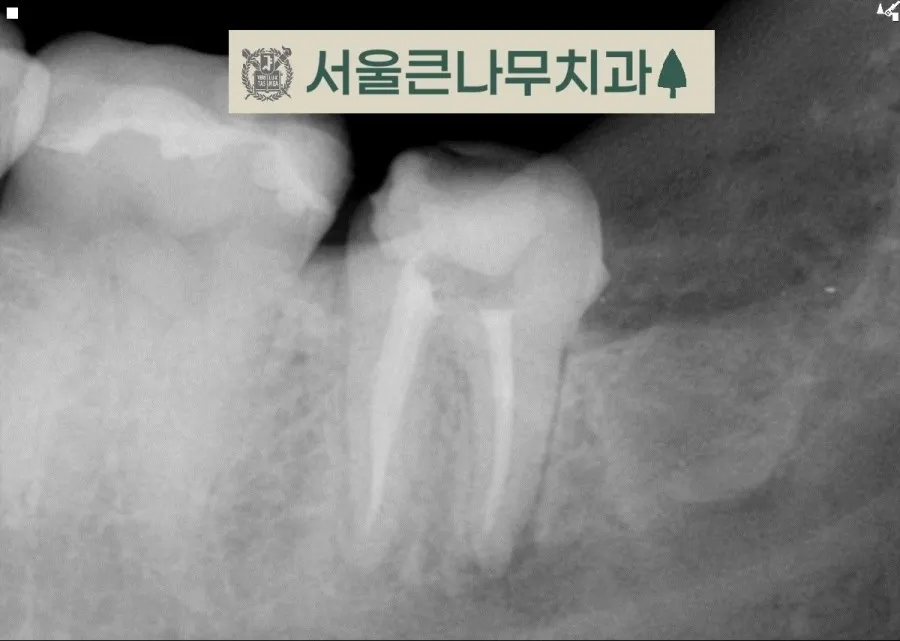

크라운을 씌운 지 1년 밖에 지나지 않았지만 뿌리끝 염증이 보이고 지속적인 통증이 있어 내원하셨습니다. 이전 크라운을 제거하고 치료에 들어갔습니다.

보철물을 제거해 보니 안에 검게 부식된 흔적이 보였고 충치가 깊어 치수가 어느 정도 드러나 있는 상태였습니다. 꽤 많은 부분을 제거하고 신경치료에 들어갔습니다.

열어보니 이미 상당히 진행된 치수염으로 인해 냄새도 나고 신경이 괴사된 상태였습니다.

이후 레진으로 벽을 만들어 주었고 치아 보강을 완료해 주었습니다.

신경을 제거하고 비어있는 신경관을 재료로 채워 완료해 준 모습입니다. 신경치료 완료 후에는 다시 크라운을 씌워 치아를 보호하게 됩니다.